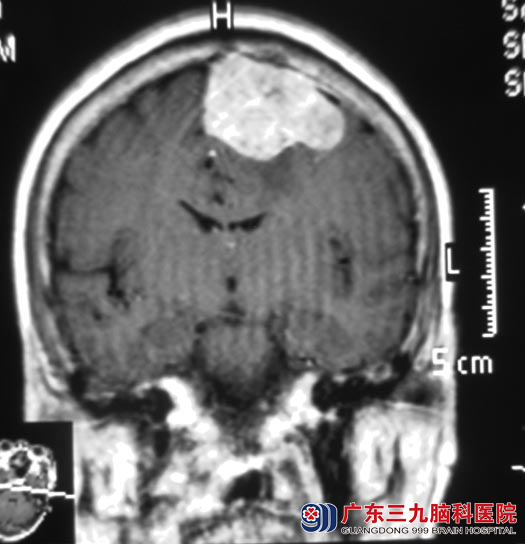

入住广东三九脑科医院综合神经外科,头颅MR检查示:“左侧大脑镰窦旁占位,大小约41.6mm×49.8mm×38.9mm,考虑脑膜瘤”。血液检查发现陈阿姨血小板比正常值低很多,经血液科会诊排除了血液病的可能性,输注血小板后陈阿姨的血小板恢复正常,整体状况均比入院时明显改善。http://www.999brain.com/

7月16日,鲁明主任主刀,在全麻下行左侧大脑镰窦旁脑膜瘤切除术,显微镜下见顶部肿瘤与硬膜粘连,包膜完整,质中偏硬,血运较丰富,广基与大脑镰相连。电凝切开肿瘤包膜,电灼、分离肿瘤,见肿瘤侵入上矢状窦内,肿瘤与脑组织粘连,镜下全切肿瘤,大小约4.5cm×4.9cm×3.5cm,术中对上矢状窦保护完好,手术顺利结束。陈阿姨已康复出院。术后病理结果为:(左侧大脑镰旁)砂粒体型脑膜瘤(WHO I级)。

▲手术前